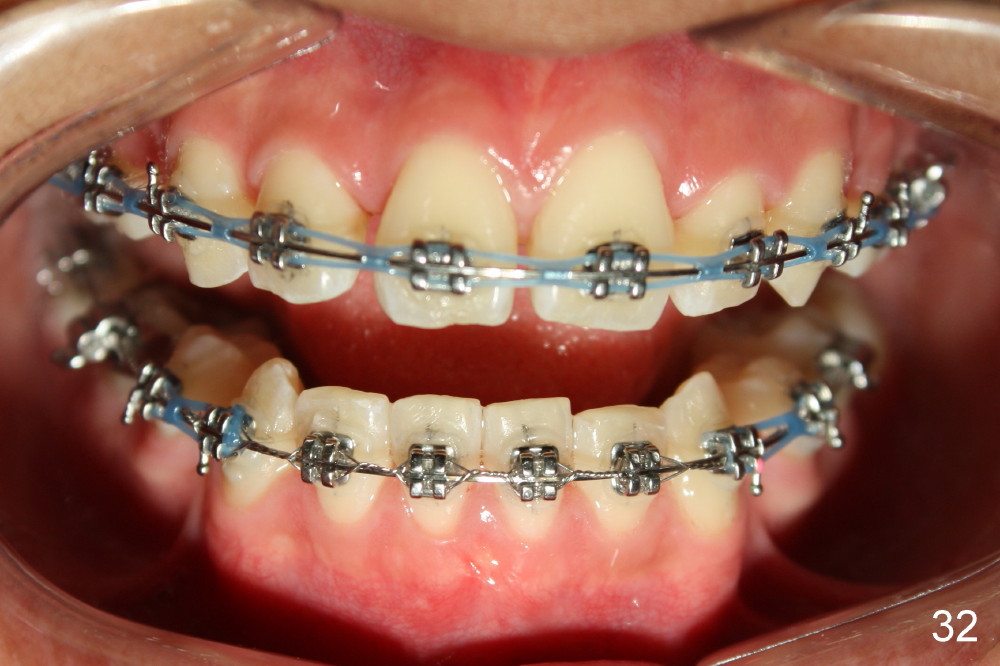

Prior to bracketing, the mesiodistal space for #18 is planned to be obtained by moving #20 and then #19 mesially (Fig.31-35, 16x16 ss). The six anterior lower teeth are tied together in a figure 8 fashion. Power chains are placed between the lower canine and the 2nd bicuspids. The upper diastemata are to be closed by power chains between the 1st molars.